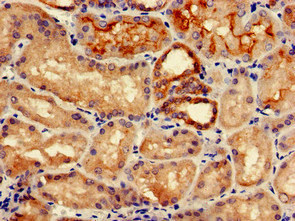

圖片:

應用范圍:ELISA, IHC

Application Recommended Dilution IHC 1:20-1:200 -